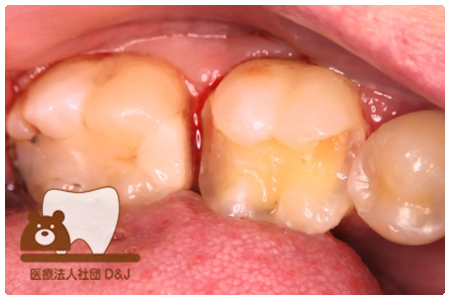

症例5フルジルコニアクラウン 右上6

治療前

治療後

46歳 女性

- 治療内容

- 虫歯を削った部分へフルジルコニアクラウンで修復を行いました。

- 治療期間

- 1カ月

- 費用

- 自費

フルジルコニアクラウン:77,000円(税込)

(R8.1月時点)

- その他の治療の費用は含まれておりません。

- リスク・副作用

- 強い力が加わると割れる可能性があります。また、噛み合わせや歯ぎしりの影響で脱離することがあります。